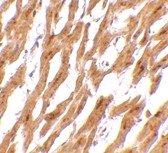

Below: Immunohistochemistry of ASAH1 in human heart tissue with ASAH1 antibody at 2.5 μg/ml.